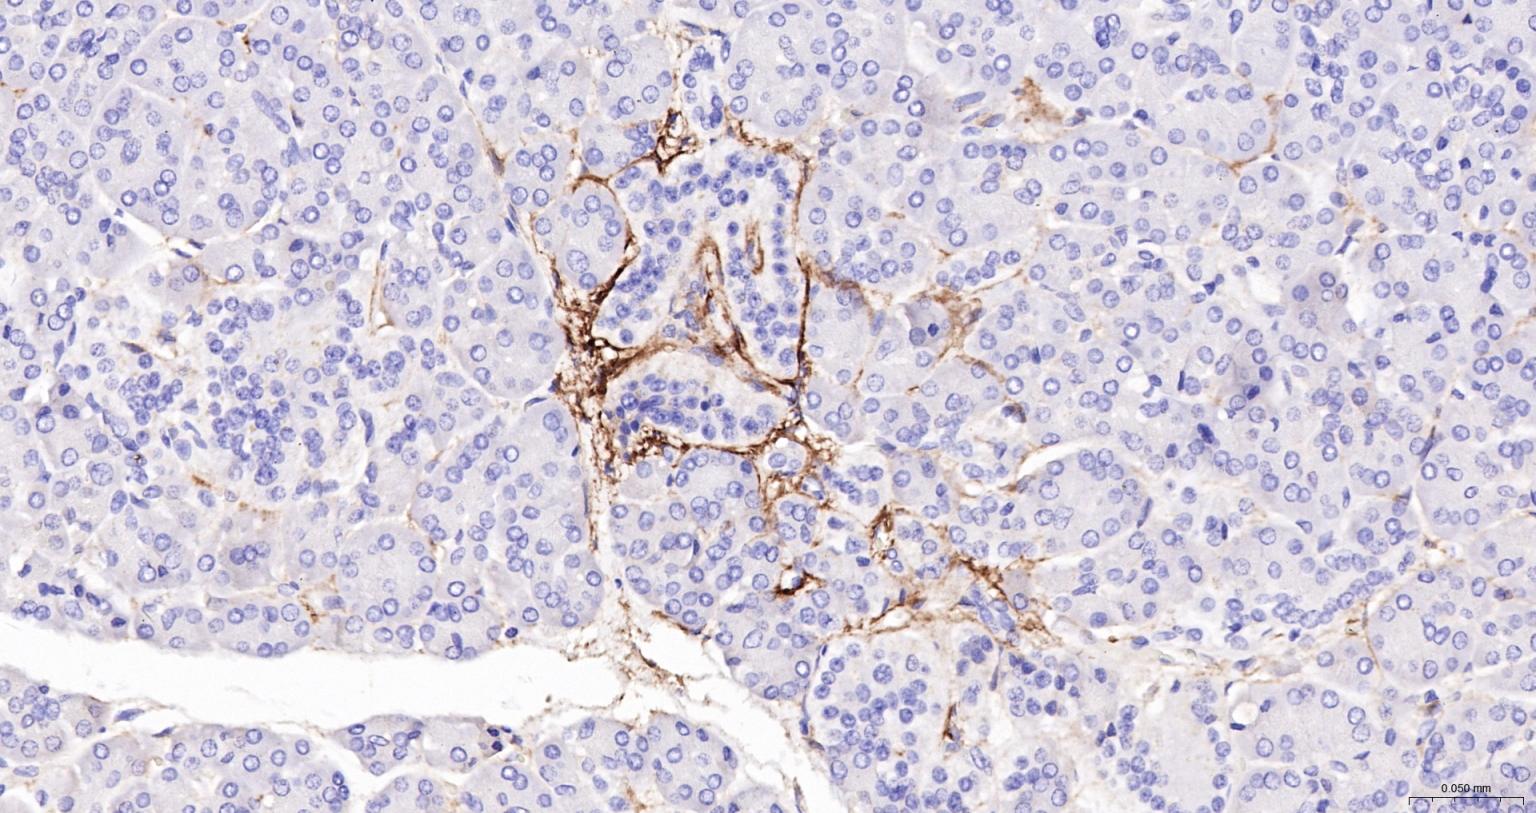

IHC-PHuman1:100-500

交叉反应: Human